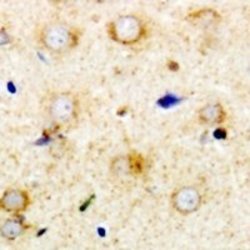

Immunohistochemistry

ABIN2967001 IHC